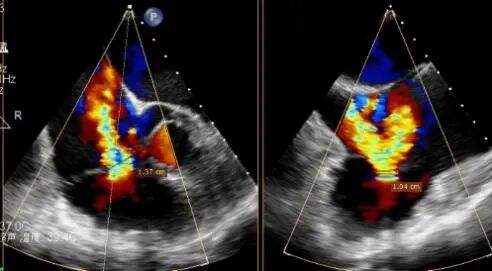

Preoperative echocardiographic evaluation: Severe tricuspid regurgitation (4+, average vena contracta 12 mm), with the regurgitant orifice located at the anteroseptal and central regions. Mild dilatation of the tricuspid annulus (average annulus diameter 41.8 mm).

Transesophageal echocardiography upon admission showed regurgitant jets at the anteroseptal and central regions.

Baseline preoperative regurgitation